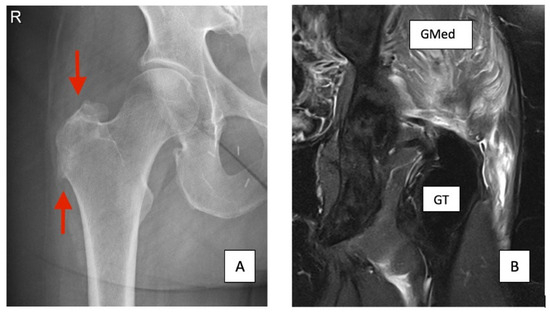

3.1. X-Ray

3.2. Ultrasound

3.3. MRI